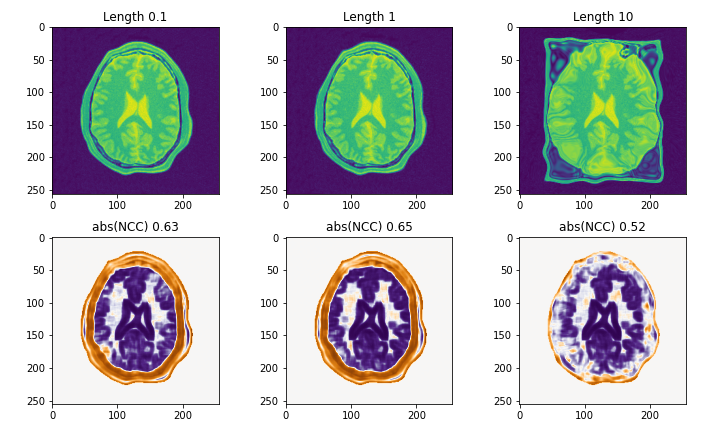

- Registrationの結果が歪である

いくつかのparameterが原因ですが,B-splineのグリッド幅を決定するFinalGridSpacingInPhysicalUnitsと更新幅への制約であるMaximumStepLengthが特に重要です.3次元画像に適用するときには,一層気にかける必要があります.

MaximumStepLengthの比較